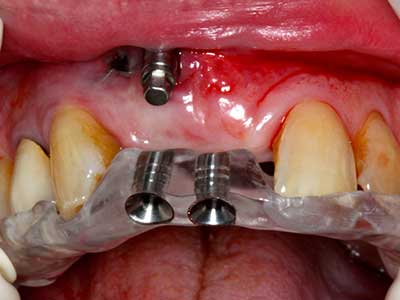

Quando le procedure chirurgiche vengono eseguite sull'osso nelle immediate vicinanze di strutture sensibili, come vasi sanguigni o nervi, gli strumenti rotanti pongono un rischio significativo di lesione iatrogena. I dispositivi piezoelettrici possono essere utili per la preparazione delle coperture ossee e la rimozione del tessuto duro in prossimità dei nervi, in particolare per la loro esposizione dopo una lesione iatrogena, ma anche durante la lateralizzazione dei nervi per le procedure di resezione e ricostruzione o il posizionamento di impianti (figg. 17-20). Il contatto leggero tra puntina piezoelettrica e nervo non causa generalmente danni, ma se si procede senza prestare attenzione con movimenti a sega o raccordi con residui di substrati ossei possono verificarsi danni al nervo temporanei o anche permanenti. Il rischio di danno, tuttavia, è considerato sostanzialmente inferiore al rischio presente utilizzando seghe o frese (Pereira, Gealh et al. 2014).